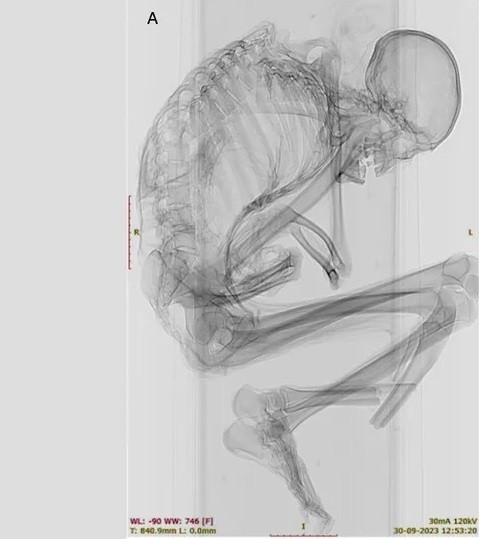

Trên xác ướp có nhiều bằng chứng về chấn thương do lực tác động mạnh cho thấy người đàn ông có thể đã thiệt mạng do đá lở hoặc sập hầm mỏ. Trong nghiên cứu mới công bố, các chuyên gia đã chụp CT và chụp X-quang để giải mã chi tiết những chấn thương nghiêm trọng có thể đã dẫn đến cái chết của người đàn ông trên. Ảnh: Francisco Garrido and Catalina Morales.

Nhiều vết nứt chưa lành được phát hiện trên phần cột sống trên của người đàn ông. Người này cũng bị gãy xương sườn, xương bả vai và xương đòn, cho thấy "một lực tác động mạnh lên một vùng rộng" ở phần lưng trên, tiết lộ rằng "phần ngực trên bên trái của ông chịu lực tác động chính". Điều này đã dẫn tới một số đốt sống bị lệch và làm xẹp lồng ngực. Ảnh: geologyin.com.

Ngoài ra, các nhà nghiên cứu đã xác định được một vết nứt ở đốt sống gần gốc cột sống của thợ mỏ, có khả năng là hậu quả của chấn thương ban đầu ở phần lưng trên. Cả chấn thương cột sống trên và dưới đều "thường liên quan đến tổn thương tủy sống nghiêm trọng và tỷ lệ tử vong cao. Ảnh: pueblodirect.com.

Nhóm nghiên cứu không phát hiện thấy thương tích nào ở hộp sọ, cổ hoặc cánh tay của người đàn ông. Điều này cho thấy vụ tai nạn xảy ra khi người thợ mỏ đang ở tư thế cúi đầu. Lúc xảy ra tai nạn lao động, có thể ông đang tập trung khai thác ngọc lam hoặc có lẽ đang cố gắng bảo vệ phần đầu bằng hai tay khi một tảng đá nặng rơi từ trên cao rơi xuống. Ảnh: pueblodirect.com.